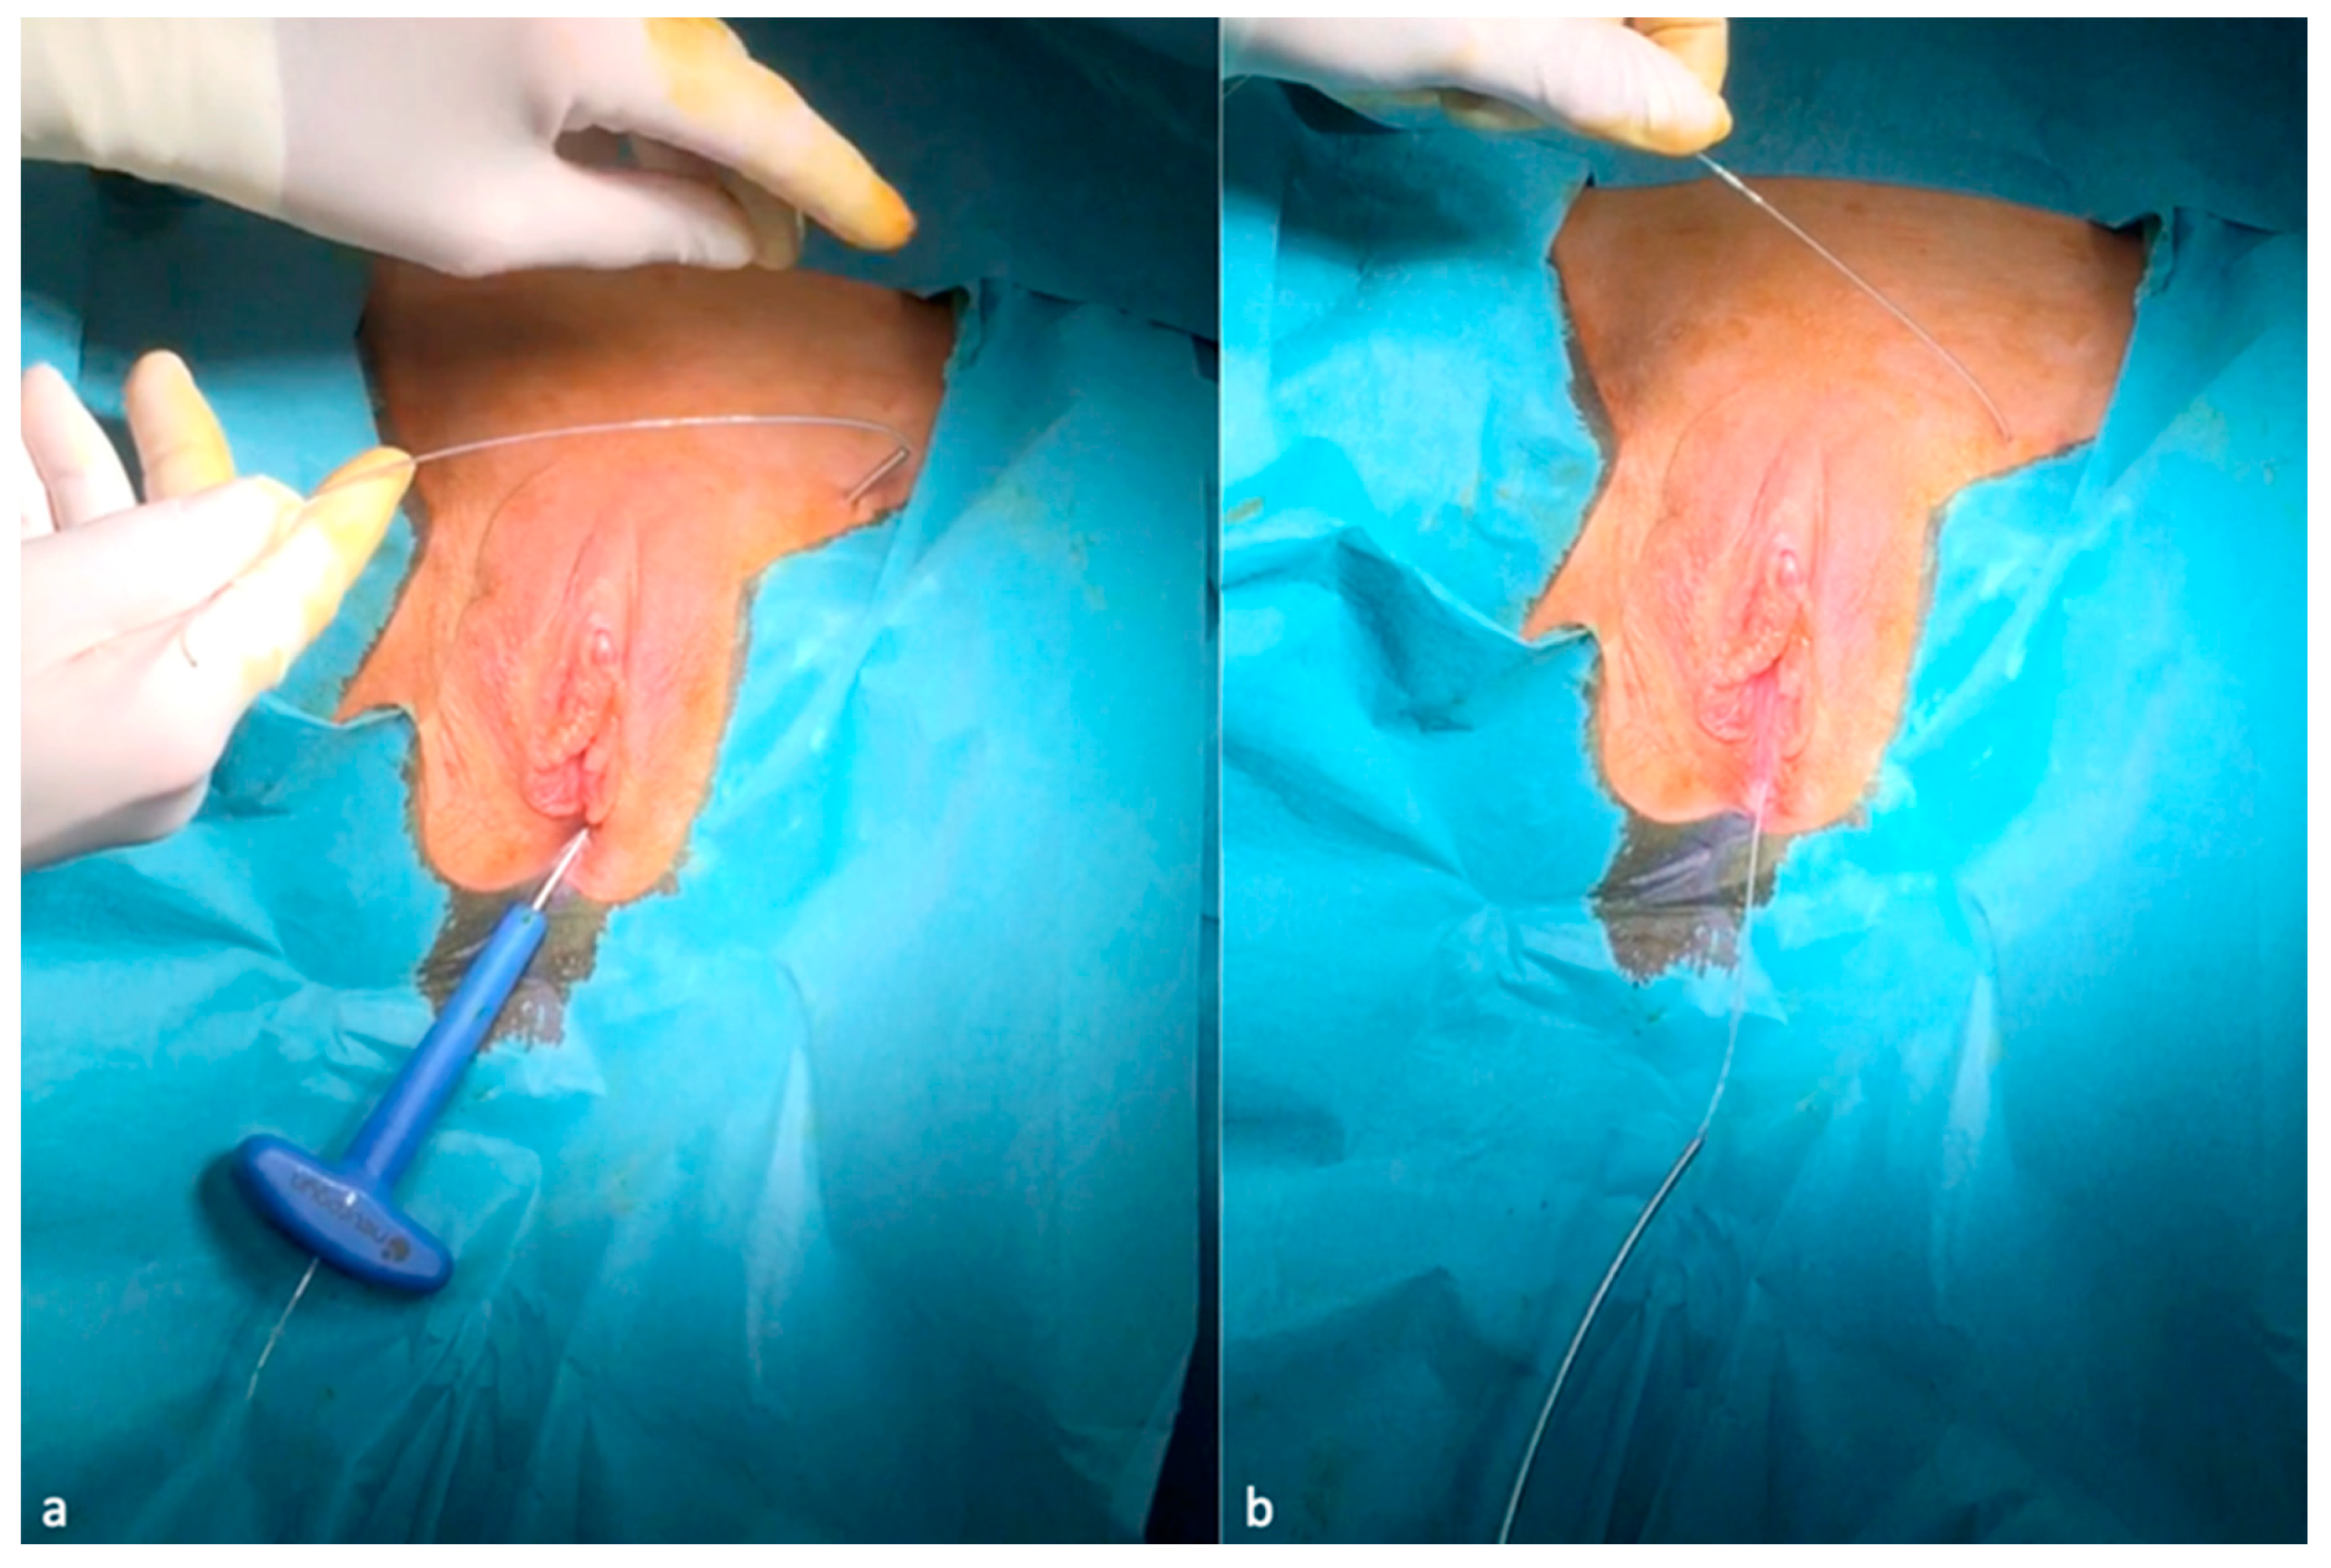

3. Genital Nerves Stimulation (GNS) Therapy

- Possover, M. A new technique of laparoscopic implantation of stimulation electrode to the pudendal nerve for treatment of refractory fecal incontinence and/or overactive bladder with urinary incontinence. J. Minim. Invasive Gynecol. 2014, 21, 729. [Google Scholar] [CrossRef]